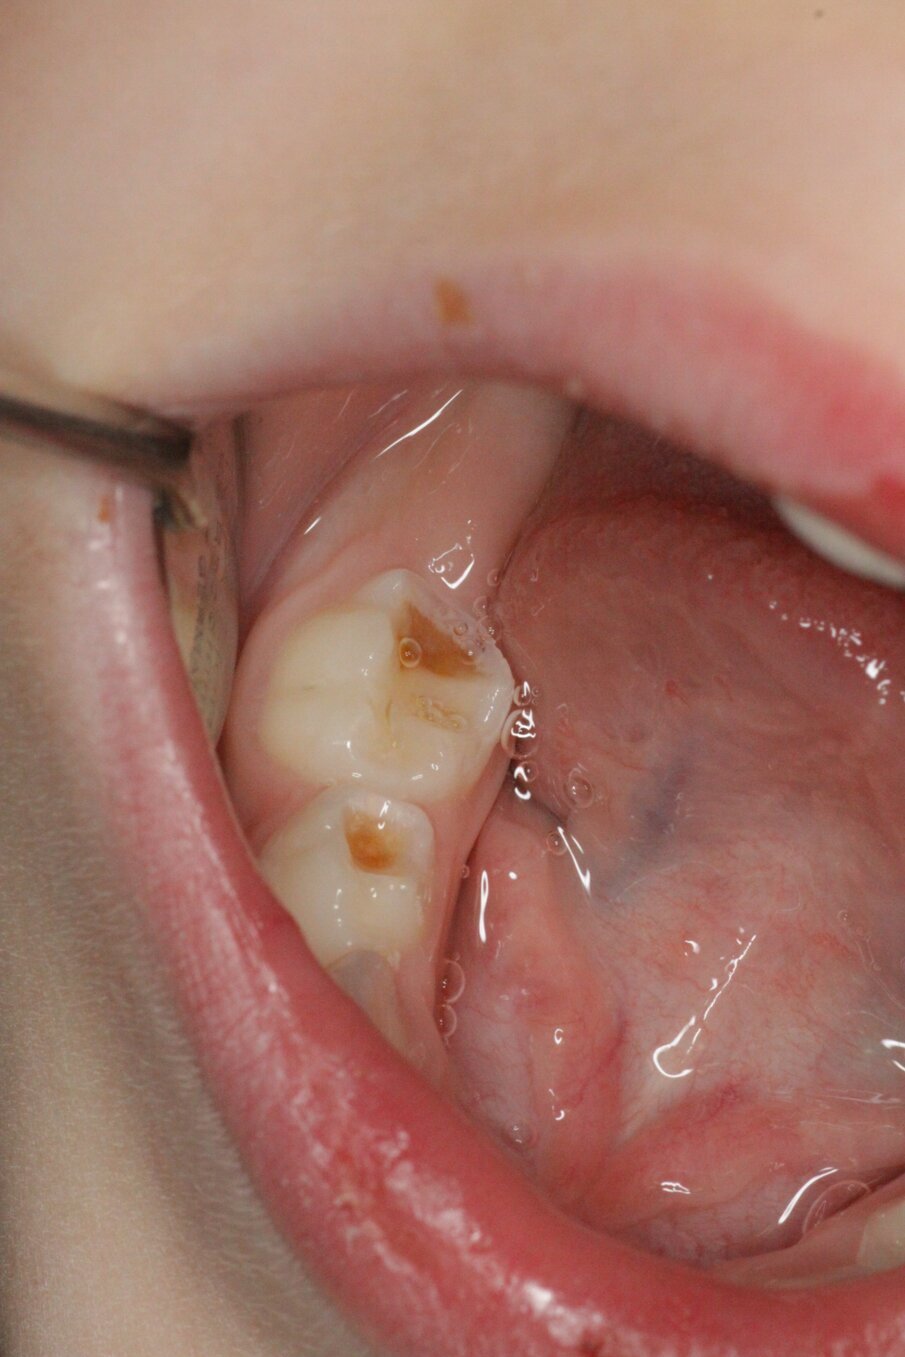

Er wordt bij periodiek mondonderzoek weinig plaque aangetroffen. Sommige laesies zijn inactief en andere worden of blijven actief (afbeelding 3a-c). De 75 werd na een half jaar van een Atraumatic Restorative Treatment (ART)-restauratie voorzien wegens gevoeligheid. Na 2 jaar trad ’s nachts pijn op aan de 64, maar deze verdween weer. Achteraf was het beter geweest als de 64 ook met ART was gerestaureerd (afbeelding 4a-b). Moeder is tevreden over de behandeling na 4 jaar, maar wij zullen nog beter ons best doen om meer zicht te krijgen op de mondverzorging thuis en daar de behandeling op afstemmen. Hoe dan ook, een narcosebehandeling is deze jonge patiënte gelukkig bespaard gebleven.

Afbeelding 4a. Bitewings na 3 jaar. Laesie 74 distaal wordt beslepen.

Afbeelding 4b. Bitewings na 3 jaar. Laesie 74 distaal wordt beslepen.